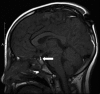

Case: We report a case of post-traumatic hypopituitarism in a 9-year-old boy who was injured in a car accident.

Outcome: Post-traumatic hypopituitarism might be caused by moderate to severe head trauma, and while this possibility has recently drawn attention in adults, few reports are available regarding children. Our patient experienced head and facial injury, resulting in post-traumatic hypopituitarism. Six hours after injury he suffered from diabetes insipidus and hormone replacement therapy was started. On day 12 he underwent facial fracture reduction under general anesthesia. On day 24 he was discharged from the hospital. One year after the injury, secretory function and water dehydration tests suggested the possibility of post-traumatic hypopituitarism.